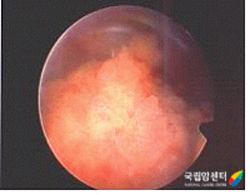

방광암의 방광내시경 사진

2009.08.20